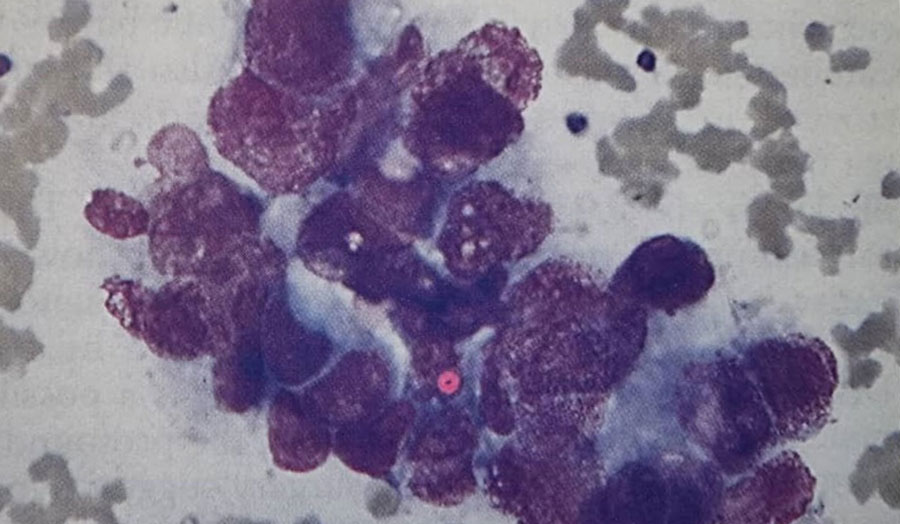

1. نظر شما در مورد شمارش افتراقی گلبولهای سفید و گسترش خون محیطی بیمار چیست؟ (شکل 63a)

گسترش خون بیمار وضعیت لکواریتروبلاستیک (Leukoerythroblastic blood film) را نشان میدهد که نشاندهنده نفوذ مغز استخوان توسط سلولهای غیرمیلوئیدی آبنرمال است. این یافته اندیکاسیونی برای بررسی مغز استخوان محسوب میشود .